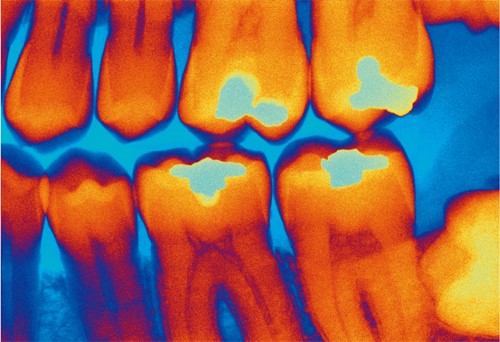

医生在进行X射线摄片时,将能感光的底片放在人体下方。当X射线透过人体时,骨骼、牙齿等组织内含有的钙质会吸收部分的射线,使到达底片的X射线减少,这样就能在底片上留下组织的影子了。这就像阳光下人的影子一样。人类第一幅X线片就是德国大科学家伦琴为他夫人所拍的手骨特写。其实不光是骨骼,其他凡是能够吸收X射线的物体,都会在感光底片上留下它们的身影。X射线就是这样一种神奇的射线。